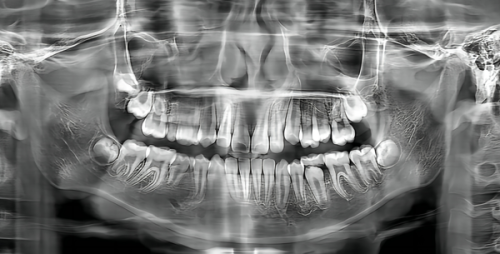

落后的治疗技术不仅治疗成效差,还可能会给患者带来更多的痛苦。这让患者在治疗时充满了恐惧和担忧。上海可恩口腔门诊部(茅台路分院)紧跟国内外口腔医学发展趋势,引进了一系列精良的口腔治疗设备和技术。比如,数字化正畸技术,能让患者提前看到牙齿矫正后的成效,精细控制矫正过程;种植牙技术采用了精良的种植系统,手术创口小、修复快、稳定性高。这些精良的技术和设备,大大提高了治疗成效和患者的舒适度,让患者不再害怕看牙。